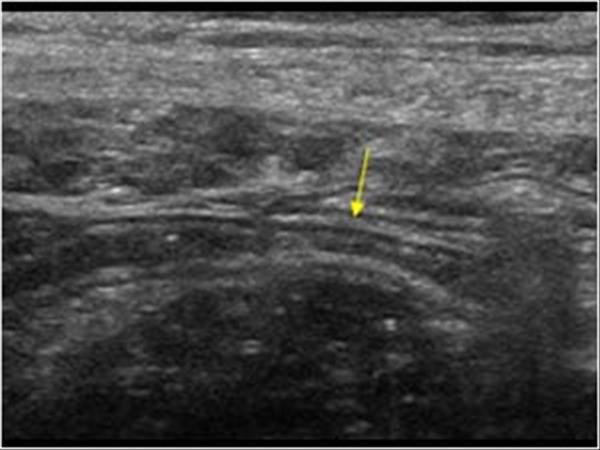

Source: imagegently.org